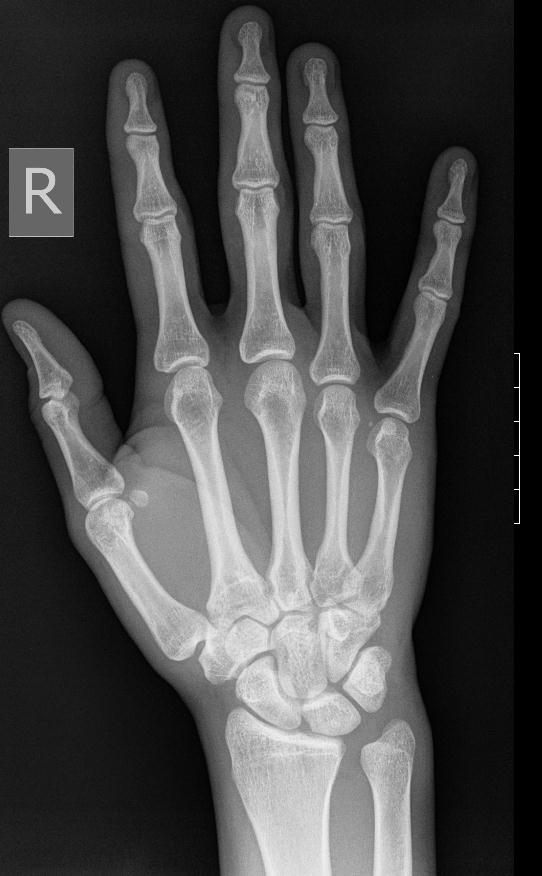

X-ray of the Right Hand

This image is in the public domain.

2. Show your students the x-ray image of the right hand. Ask them to write down what they see—the colors, the light, the dark, the clarity. Where are these aspects located in the X-ray?